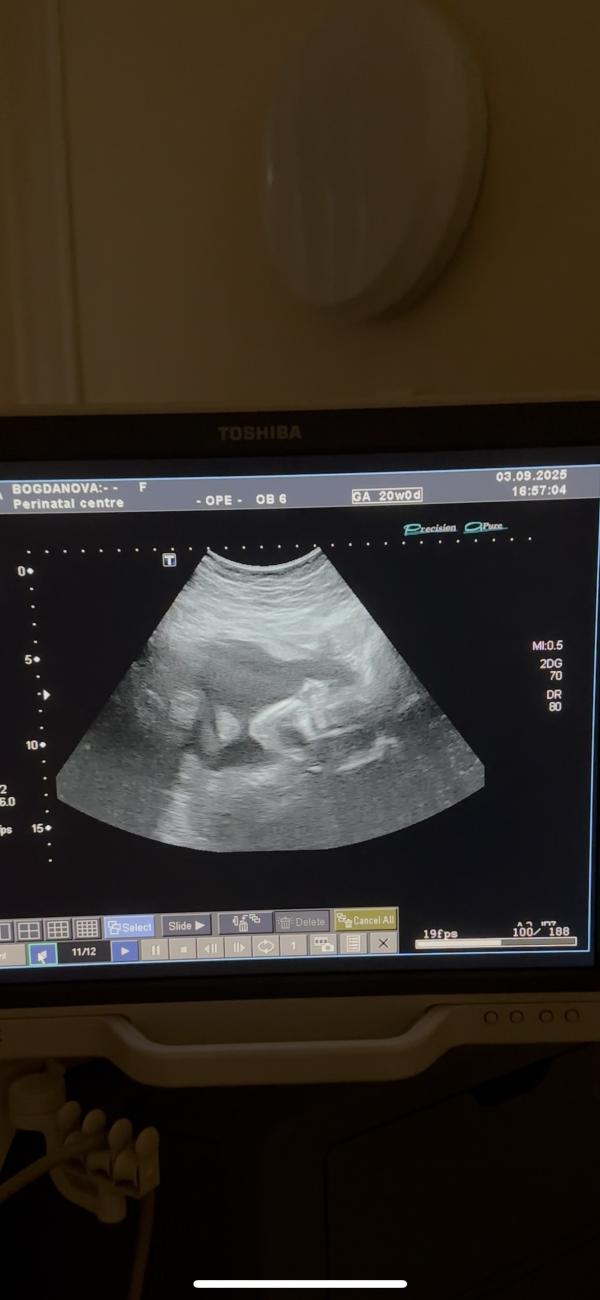

Второй скрининг позади, развивается отлично, подтвердили, что у нас девочка (хотя Еся немного прикольнулась с пуповиной между ног 😂)

Дали заснять парочку видео на память, показали подробно со всех сторон малышку мужу, перинатальный в этом плане вообще огонь!!

У меня какие-то щенячие восторги каждый раз, когда ее вижу🥹 каждое узи как Новый год)) очень мило позевала, помахала ручкой и даже показала нам всем Фак)))